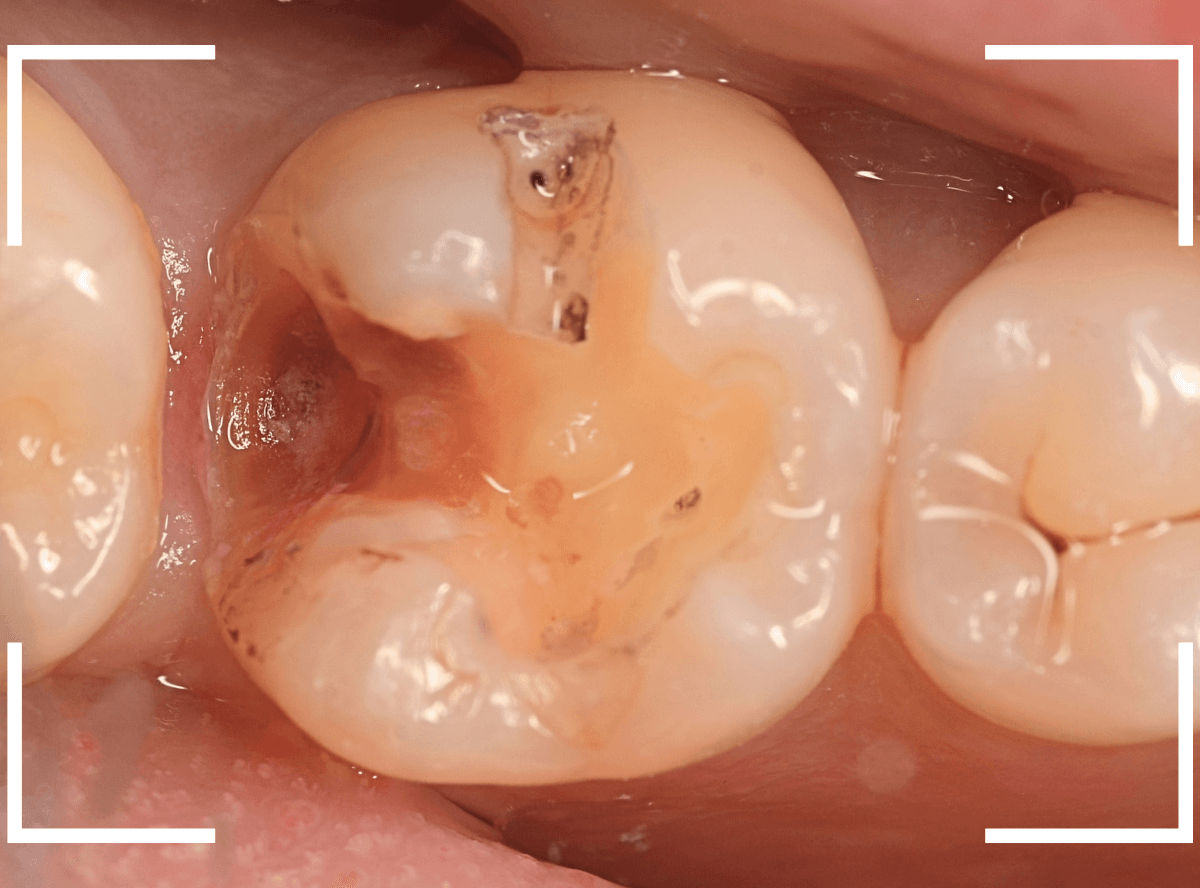

Case.14 インレーの下の歯肉まで広がった虫歯

「下の奥歯が噛むと痛む」という症状で来院された患者さんのケースです。

お口の中の状態を確認すると、奥歯の端に穴が開いているのが見えます。

ここかな?

レントゲン写真で確認します。

やはり、奥歯の端が大きな虫歯になっています。

青いラインが歯の神経、赤いラインが虫歯です。

レントゲン写真上では虫歯が神経まで達しているように見えます。

これは、神経を取らないとダメかもしれません。